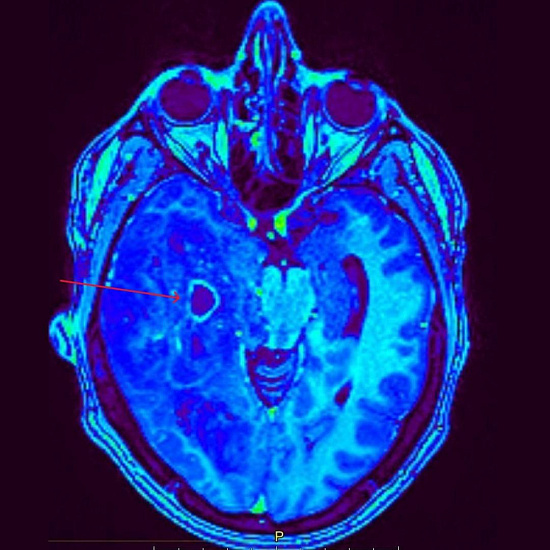

При проведении МРТ головного мозга выявлена опухоль правой височно-теменной области с переходом на островок, вовлечением базальных ядер справа и мозолистого тела с выраженным перифокальным отеком с дислокацией срединных структур мозга влево, компрессией правых бокового и третьего желудочков, среднего мозга.

При введении контрастного препарата визуализировался участок интенсивного кольцевидного накопления по периферии кистозного компонента опухоли.